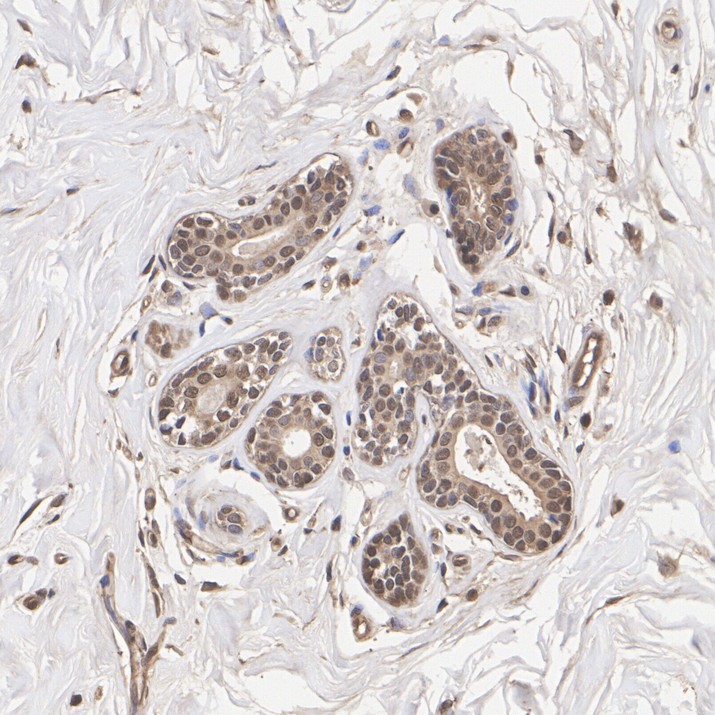

Immunohistochemical analysis of paraffin-embedded human breast cancer tissue with Rabbit anti-LDHA antibody (HA751477) at 1/20,000 dilution.

The section was pre-treated using heat mediated antigen retrieval with Tris-EDTA buffer (pH 9.0) for 20 minutes. The tissues were blocked in 1% BSA for 20 minutes at room temperature, washed with ddH2O and PBS, and then probed with the primary antibody (HA751477) at 1/20,000 dilution for 1 hour at room temperature. The detection was performed using an HRP conjugated compact polymer system. DAB was used as the chromogen. Tissues were counterstained with hematoxylin and mounted with DPX.